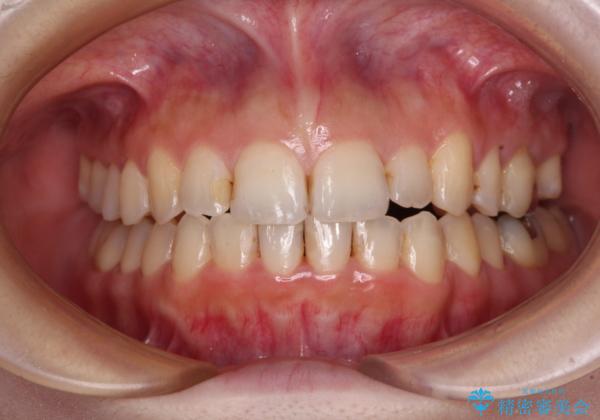

顕著な八重歯をインビザラインで治せるところまで改善

- 顕著な八重歯など、上下前歯のデコボコとスペースを気にして来院された患者様です。

補助装置だけでなく、部分的にワイヤー矯正も使用しましたが、上下のスペースは改善しきれず、側切歯(前から2番目の歯)や顕著な八重歯は、インビザラインで治療するには限界があることがよく分かりました。

より良い仕上がりを希望される場合には、ワイヤー装置による矯正治療がお勧めとなります。